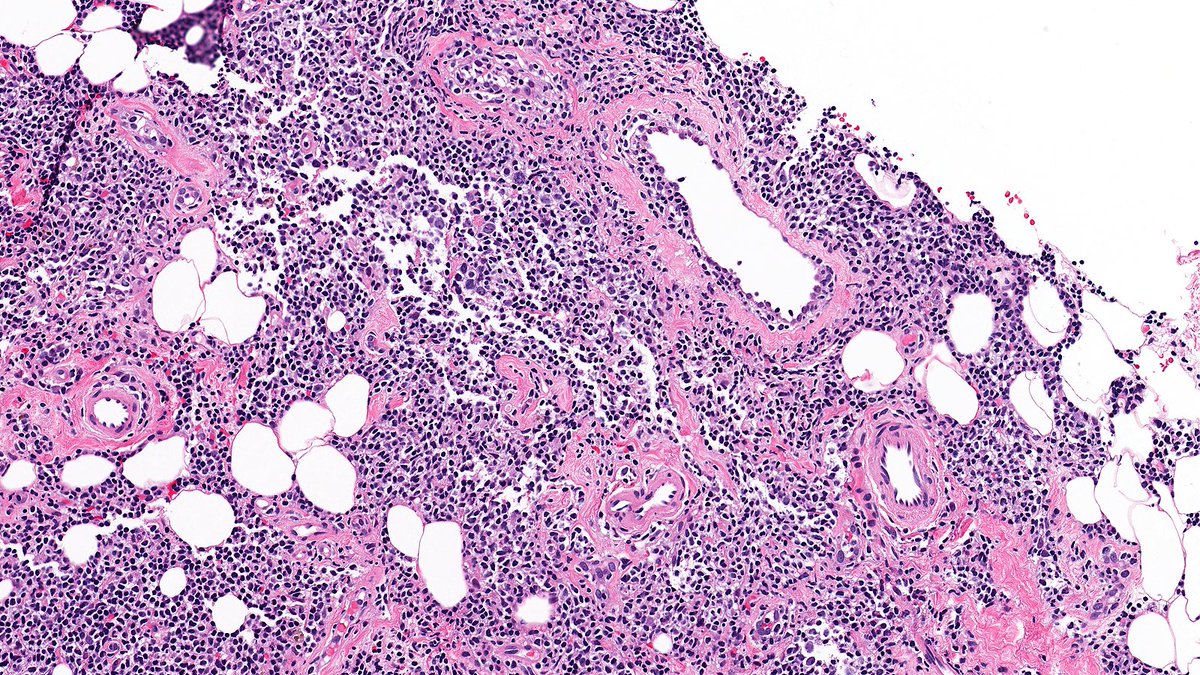

No doubt—you all crushed it! 💯 The answer: B-cell lymphoma. This one’s a marginal zone lymphoma of the breast—rare, and a great mimicker of lobular carcinoma. Hope this was a helpful review of the lobular carcinoma differential! #PathX #PathTwitter #breastpath #PathQuiz

Raza Hoda MD (@razahoda) 's Twitter Profile Photo